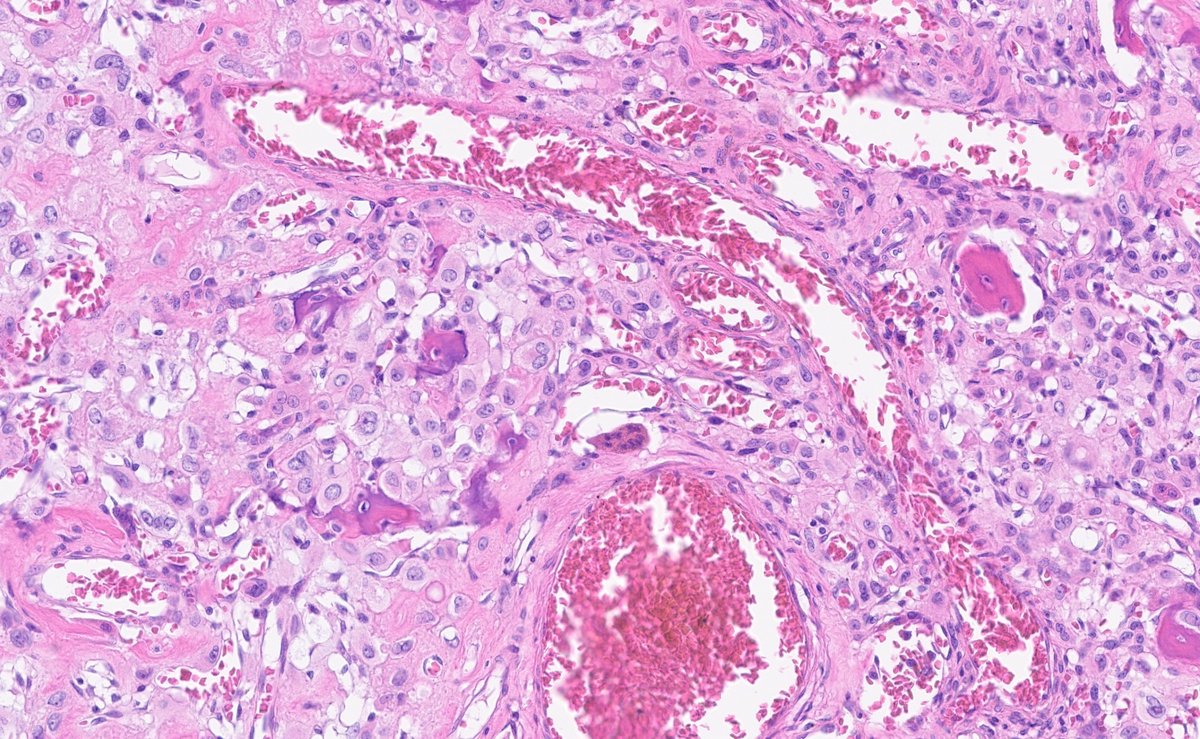

Patient presented with a cough and a 2cm endobronchial mass- very rare tumor in this location- very striking histology #pathtwitter #pulmpath #surgpath